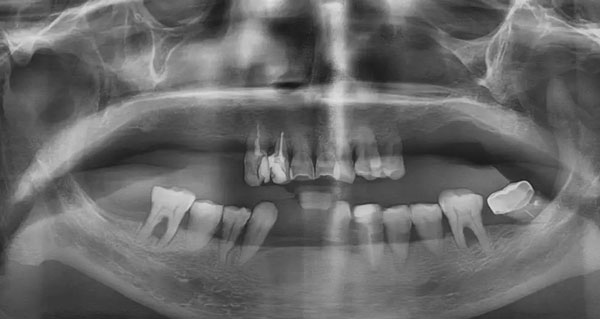

經(jīng)過全面的檢查和細致的溝通,新橋光華店種牙團隊為鄧女士量身定制了半口即拔即種-即刻負重修復方案,通過在上頜種植6顆植體,即可恢復12顆牙齒的咀嚼功能。面對超出預期的治療費用,夫妻倆斷然拿出了自己房子的部分裝修款。而這樣堅決的原因,余先生用自己瀟灑的人生態(tài)度做了最好的注解。

鄧女士種牙前后全景片對比